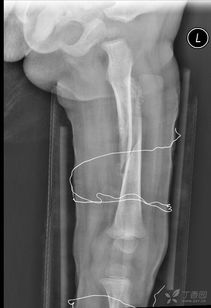

我們知道,這些微量元素是形成和發(fā)育骨骼的重要成分。另外在治療期間可以進(jìn)行物理方面的治療與護理,如按摩,讓患處的血液循環(huán)變得好起來(lái),這對于打著(zhù)鋼板的患處是很有好處的,預防因長(cháng)時(shí)間不活動(dòng)導致的肌肉萎縮現象的發(fā)生。